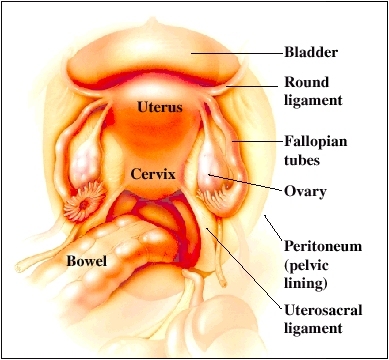

The picture above shows normal organs. Your healthcare provider can mark where you have growths of endometriosis tissue. These are called implants.

Staging depends on certain factors. These include:

Number, size, and site of implants

Presence and extent of adhesions

Involvement of other pelvic organs